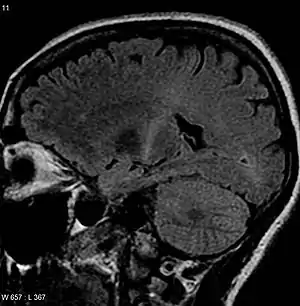

Для візуалізації стану нервової тканини використовують МРТ (КТ використують у пацієнтів, у яких проведення МРТ протипоказане, наприклад у тих, хто має електрокардіостимулятор). Зміни найкраще видно у T2-режимі.[130] На МРТ буде видно ознаки зменшення кількості нейронів, волерівську дегенерацію аксонів, демієлінізацію та відсутність ознак запалення.[131]

При дослідженні кори можливі ділянки зменшеної щільності, хоча остання ознака не є постійною та специфічною.[132] Наявність таких ділянок пов'язують з накопиченням заліза в астроцитах та мікроглії (теорію підтримують не всі дослідники).[130][133] Наявні симетричні ділянки підвищеної щільності (тільки на МРТ) за ходом кірково-спинномозкових шляхів, які найкраще виявляються в головному мозку, менше в спинному мозку (при використанні КТ буде спостерігатися зниження щільності).[134] Ще одна можлива ознака — атрофія у лобній частці, яка полягає у зменшенні кількості білої речовини, а саме аферентних волокон до лобної кори.[135][136][137] Зміни в білій речовині у вигляді гіпертензивних вогнищ знаходять у субкортикальних ділянках, вздовж волокон, що прямують від кори та утворюють променистий вінець, ніжки мозку та покрив моста. Ці зміни корелюють з патоморфологічними змінами, які полягають у волерівській дегенерації та демієлінізації, заміні нормальної паренхіми сполучною тканиною.[134][138] МРТ спинного мозку часто дає нормальну картину. З можливих змін можна відзначити помірні гіпертензивні ділянки у передніх рогах, «сплющення» передніх та бічних рогів (спинний мозок набуває форми оберненої підкови), однак ці зміни нечасті.[132][134][139]

Варто зазначити, що МРТ не варто використовувати, коли є безсумнівні клінічні ознаки бічного аміотрофічного склерозу. Загалом діагноз «бічний аміотрофічний склероз» ставиться на основі клінічних даних.[137]